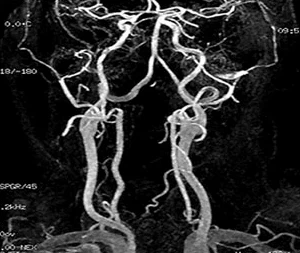

혈관 영상 초음파 검사방법

혈관의 종·횡단면 영상을 통해 혈전이나 협착의 진행 정도와 Plaque(플라그)의 형태 등 혈관상태를 기록하며, 혈류의 파형과 혈류량 및 속도 등으로 혈류의 상태를 알 수 있습니다.